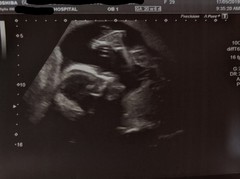

Hoping these are the correct edited ones!!

We nearly missed our anatomy scan completely thanks to the buses that either never turned up or got delayed/took ages to get to the hospital as it was packed. Thankfully someone had cancelled theirs just after when ours would have been so they very kindly squeezed us in. Would've completely understood if they couldn't have done it. All is looking okay. Placenta is definitely at the front but I think we're slowly getting there with feeling movements, and he still appears to be a boy 💙😊 I'm so, so relieved.

Congratulations @UnicornsandRainbows1 I'm glad you got to have your scan and that everything looks great! Your baby looks lovely. The pictures reminded me of my can of my DD. I just thought it was so amazing to see her perfect little spine. So intricate and perfect :) am I weird?! Lol xxxxxx

@54ChikiTIKI Not weird at all! 😊 It's so odd. I don't remember my DD's scan being so clear, but it's so odd how formed it is. I know it's 20 weeks but it's just insane!

@UnicornsandRainbows1 what a stunning and clear scan picture - congratulations x

Fantastic news on your scan @UnicornsandRainbows1 - that's an amazing pic of your son's spine! Ii'm so glad things are going okay for you.